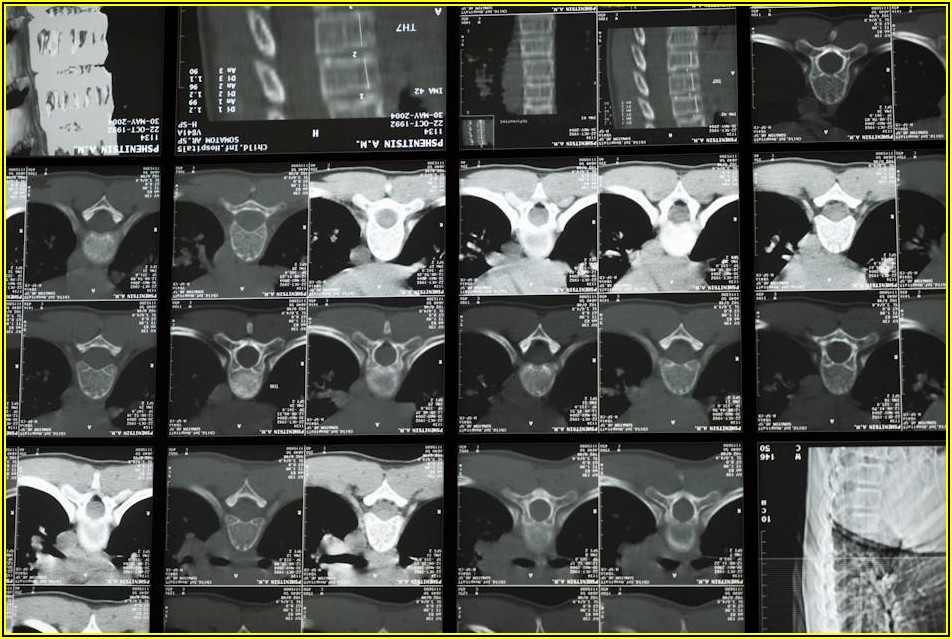

CT 검사 비용, 부위별 상세 비교 가이드

미래의 건강을 위한 투자, CT 검사! 하지만 어떤 부위를 찍어야 할지, 그리고 그 비용은 얼마인지 궁금하시죠? 뇌, 폐, 복부 등 CT 촬영 부위에 따라 비용이 크게 달라지기 때문에, 미리 정보를 파악하는 것이 중요합니다. 본문에서는 각 부위별 CT 검사 비용을 상세하게...